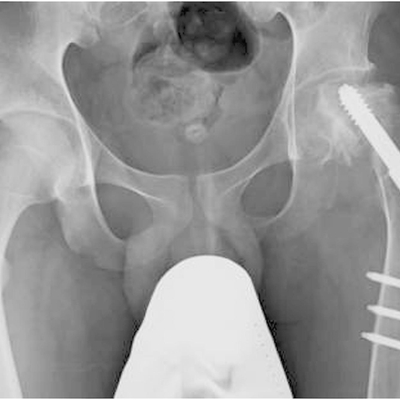

Click on an image below to view more info.